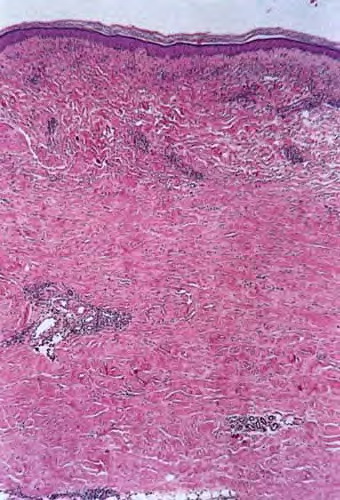

morphea